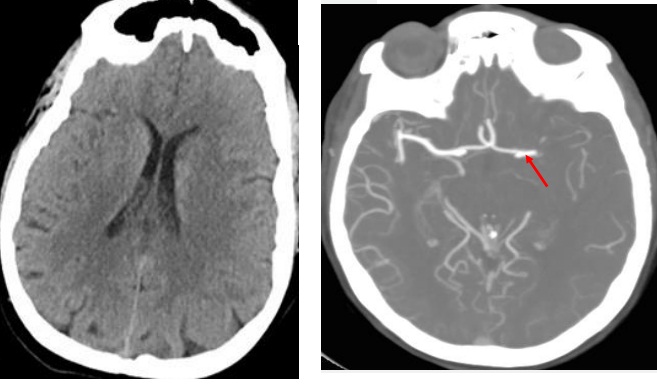

120接到患者后10分钟到急诊,急诊医生发现患者意识障碍,右侧肢体全瘫(疼痛刺激无反应),初步考虑脑中风,测血压155/95mmHg,体温36.8℃,心率90次/分,氧饱和度93%,立即给予心电监护,吸氧,输液急救处理,并拨打了我的会诊电话。短暂沟通后,我怀疑患者中风了,首先需要鉴别脑梗死和脑出血,电话中告知急诊科立即完善头颅CT及血管检查,因为患者病情较重,需考虑大血管病变。10分钟后完成了头颅CT显示:未见出血(因为时间较短,梗死未显影),诊断“急性脑梗死”,CT血管检查显示:左侧大脑中动脉闭塞。

左图CT显示未见出血;右图CT血管显示左侧大脑中动脉闭塞